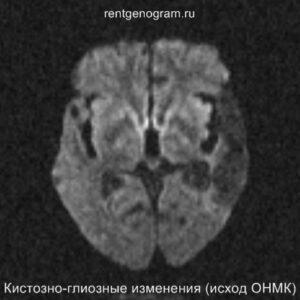

Хроническая фаза (более 6 недель)

В хроническом периоде наблюдаются процессы репарации и пролиферации, что ведет к обратному развитию вазогенного отека и восстановлению ГЭБ, что проявляется полным отсутствием контрастного усиления в зоне поражения. В местах энцефаломаляции формируются ликворные кисты (лакунарный инсульт) или происходят кистозно-глиозные изменения. Также фиксируется снижение кровотока или полная окклюзия артерии в области инфаркта.

Может начать происходить гибель аксонов нейронов, входящих в пирамидный тракт (дегенерация Тюрка-Валлера), создавая выраженную зону глиоза, которая повторяет ход пирамидного тракта. Высокий МР-сигнал на DWI полностью исчезает. Зона кистозно-глиозных изменений может приводить к тракционной дилатации полостей, что вызывает асимметричное растяжение желудка, прилегающего к зоне глиоза (гидроцефалия ex-vacuo).